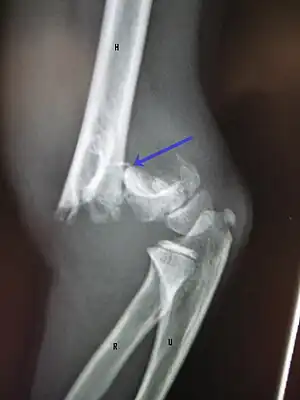

A supracondylar humerus fracture is a fracture of the distal humerus just above the elbow joint. The fracture is usually transverse or oblique and above the medial and lateral condyles and epicondyles. This fracture pattern is relatively rare in adults, but is the most common type of elbow fracture in children.[1] In children, many of these fractures are non-displaced and can be treated with casting. Some are angulated or displaced and are best treated with surgery. In children, most of these fractures can be treated effectively with expectation for full recovery.[2] Some of these injuries can be complicated by poor healing or by associated blood vessel or nerve injuries with serious complications.

A supracondylar humerus facture is diagnosed by x-ray and the injured limb will be examined to assess the surrounding soft tissue, neurovascular status, and to identify any other injuries to the affected area.[5] Pain, swelling, and deformity near the elbow or arm area is common and a bleed near the fracture may result in an effusion in the elbow joint. With severe displacement, there may be an anterior dimple from the proximal bone end trapped within the biceps muscle. The skin is usually intact. If there is a laceration that communicates with the fracture site, it is an open fracture, which increases infection risk. For fractures with significant displacement, the bone end can be trapped within the biceps muscle with resulting tension producing an indentation to the skin, which is called a "pucker sign".